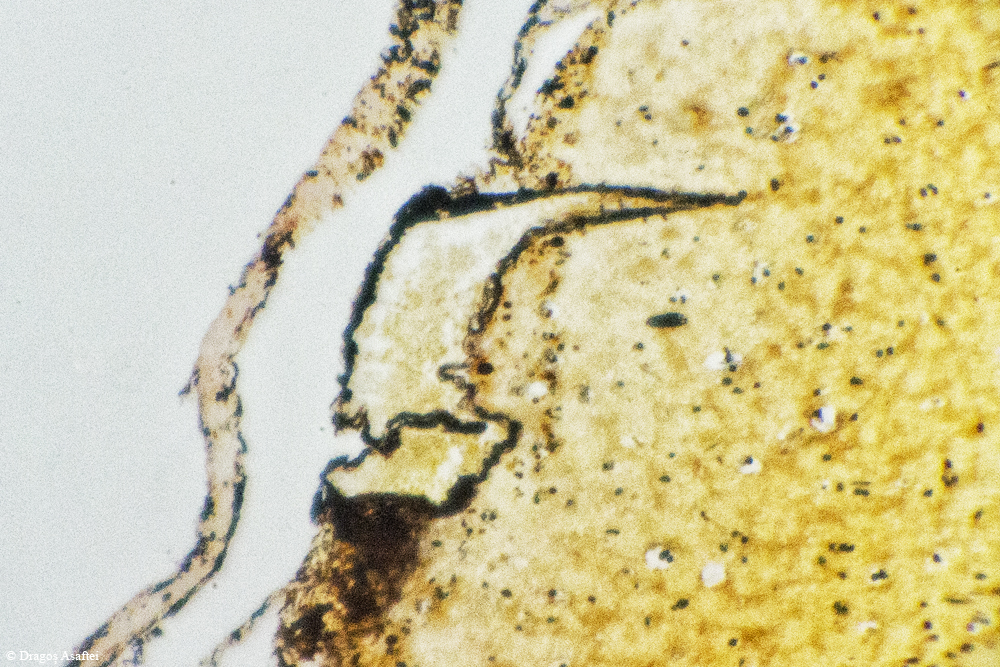

Nu știam de această metodă sau de o altă metodă viabilă pentru fotografierea prin microscop, a fost un lucru de moment care a prins foarte bine. Aveți mai jos fotografii cu următoarele țesuturi (în ordine): vena, os, cerebral, adipos, splina, mușchiul inimii, mușchi striat, mușchi, inimă.

tesutul adipos e mai mult piele si tesut celular subcutanat cu anexe(glade sebacee si sudoripare) printre care se afla si asa un tesut adipos